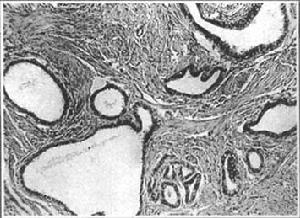

(四)、慢性間質性輸卵管炎(chronicinterstitialsalpingitis):為急性間質性輸卵管炎遺留的慢性炎症病變,多與慢性卵巢炎並存。可見雙側輸卵管增粗、纖維化,在其肌層中、腹膜下可有小膿灶殘留。臨床表現為附屬檔案增厚或條索狀增粗。鏡檢輸卵管各層均有淋巴細胞、漿細胞廣泛浸潤。此外尚可形成一種峽部結節性輸卵管炎,是輸卵管慢性炎症病變的殘留。病變主要局限於輸卵管峽部。這類病例在峽部出現明顯的結節,結節有時可能很大,類似宮角的小纖維樣腫瘤。鏡檢肌層異常增厚,管腔內膜皺襞可分別捲入肌層,形似子宮內膜異位症,可由其缺乏子宮內膜間質而區別,個別肌層有淋巴細胞、漿細胞浸潤。